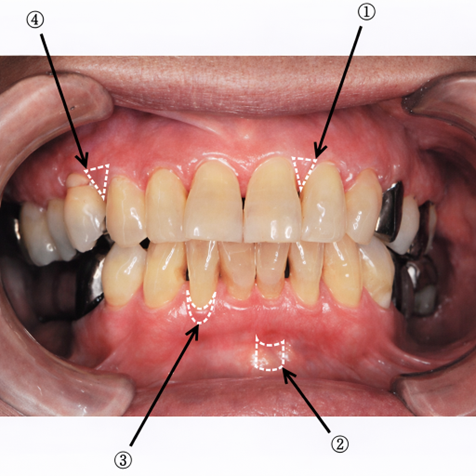

午前-69

口腔内写真を別に示す。 前歯部を対象としたPMA Indexの評価部位はどれか。2つ選べ。

a. ①

b. ②

c. ③

d. ④

解答を見る

a.c